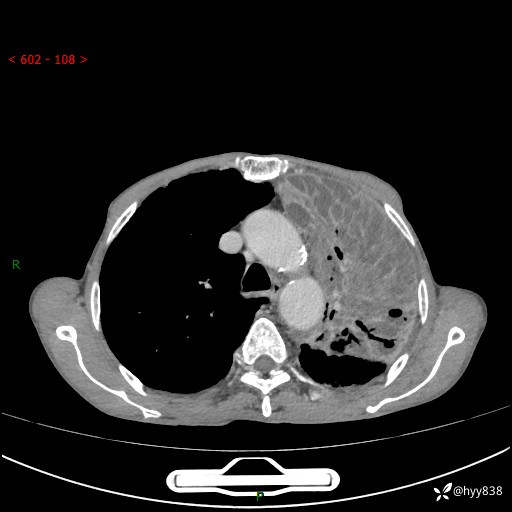

老年男性,反复咳嗽、咳痰、气喘10余年,再发3天。大叶性实变+胸膜病变-结果公布

胸部CT平扫+增强